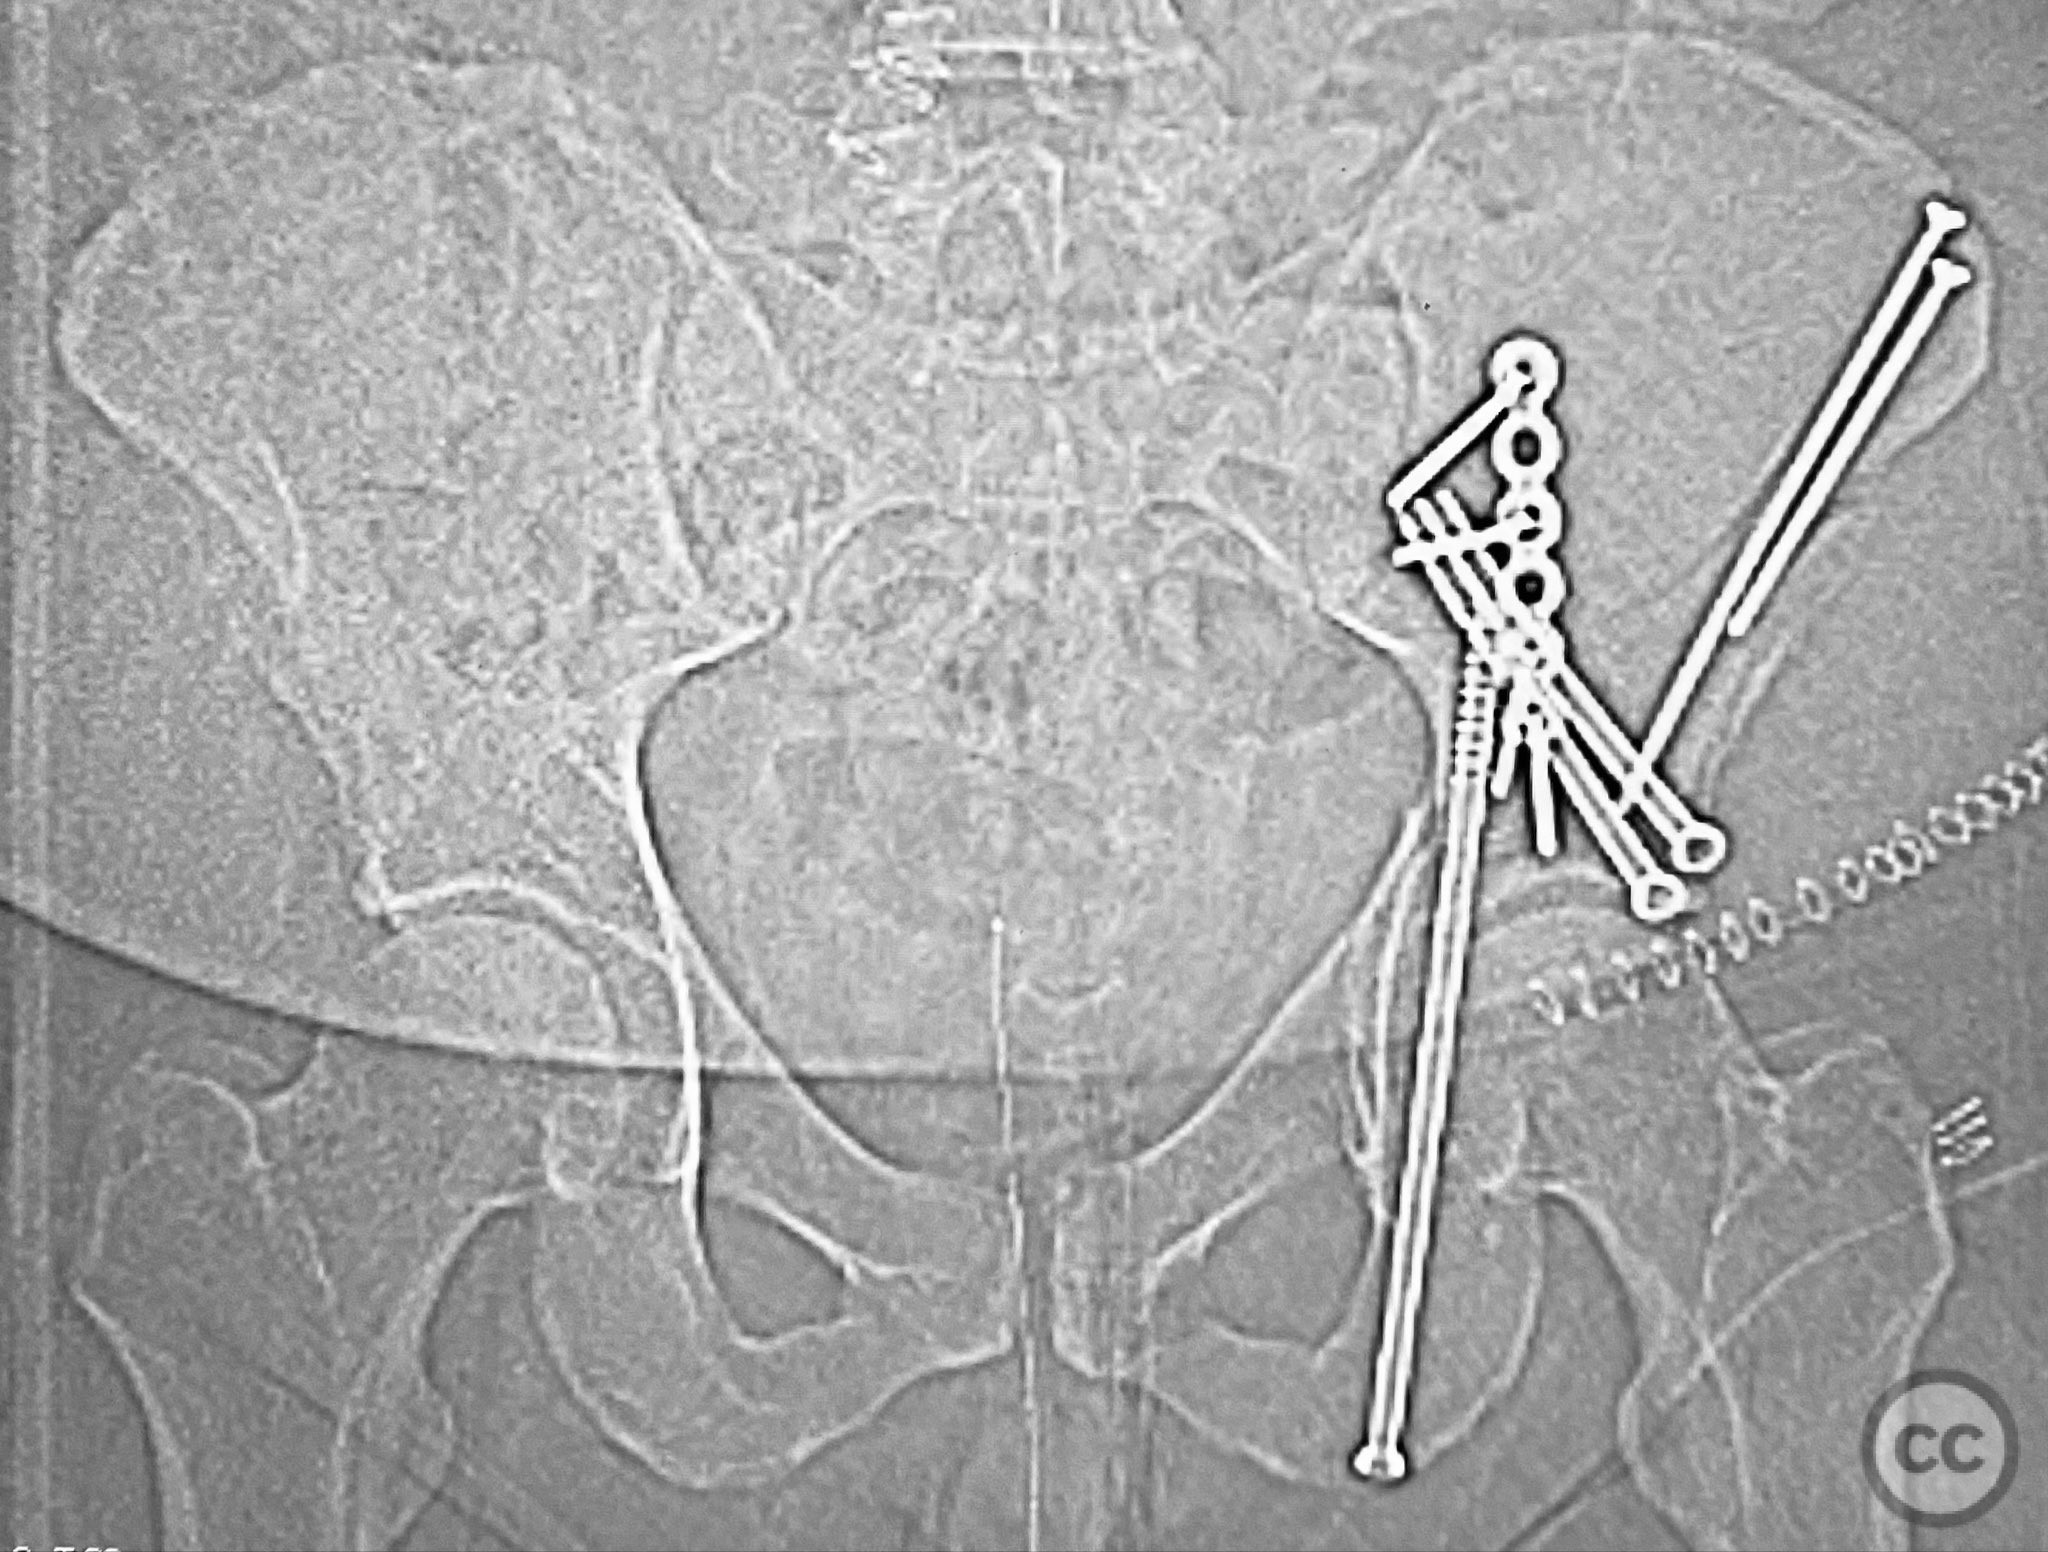

Clinical and radiological findings:  A patient presented with a displaced associated both column acetabular fracture, characterized radiographically by the presence of the "spur sign" on the anteroposterior (AP) pelvis film, indicating the caudal aspect of the intact ilium exposed by medial displacement of the articular fragments. The spur was more clearly visualized on the obturator oblique rendered image. Axial computed tomography (CT) images demonstrated the intact ilium, medially displaced anterior column (AC) and posterior column (PC) fragments, and provided detailed visualization of surrounding soft tissues, including vascular structures enhanced by contrast. Multiplanar CT reconstructions (axial, sagittal, coronal) and 3D renderings were utilized for comprehensive fracture and soft tissue assessment. The patient’s overall clinical condition was a significant factor in surgical planning.

Planning remarks:  The preoperative plan involved open reduction and internal fixation (ORIF) of the anterior column via the ilioinguinal approach, utilizing two separate windows for exposure and reduction. Given the patient’s clinical status, a staged approach was selected: initial AC reduction and fixation, with planned subsequent percutaneous reduction and fixation of the PC. Implant positioning during the first operation was planned to avoid obstructing subsequent percutaneous PC fixation.

Anatomical surgical approach:  A classical ilioinguinal approach was performed, with two windows developed: the lateral window between the musculus sartorius and musculus tensor fasciae latae, and the middle window between the musculus iliopsoas and external iliac vessels. Subcutaneous dissection was performed to create two opposing slabs of adipose tissue ("walls of fat"), minimizing random subcutaneous incisions. The anterior column fragment was exposed, reduced anatomically, and fixed under direct visualization. At a subsequent stage, percutaneous reduction and fixation of the posterior column were performed under fluoroscopic guidance, with careful trajectory planning to avoid interference from previously placed AC implants.

The operative sequence was dictated by the patient’s overall clinical status, necessitating staged management. Intraoperative attention was paid to implant placement during AC fixation to preserve access for subsequent percutaneous PC fixation. Postoperative CT confirmed satisfactory reduction and fixation of both columns, with appropriate implant positioning and no evidence of neurovascular compromise or significant soft tissue complications.